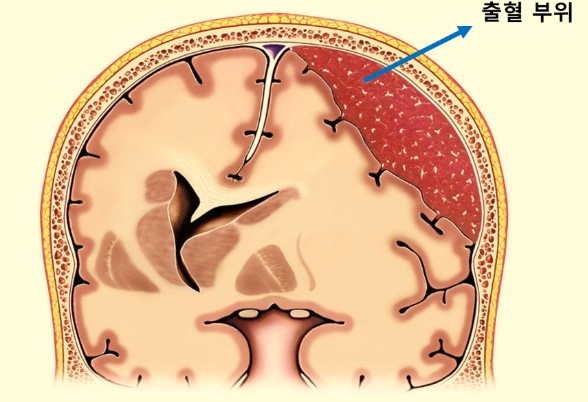

급성 경막하 출혈(Acute subarachnoid hemorrhage, SAH)은 뇌와 척수를 둘러싸고 있는 경막 밑 공간에 출혈이 발생하는 질환입니다. 급성 경막하 출혈은 뇌졸중의 한 종류로, 뇌졸중 중에서도 가장 치명적인 질환 중 하나이므로 주의가 필요합니다.

급성 경막하 출혈의 가장 흔한 원인으로는 뇌동맥류 파열입니다. 뇌동맥류는 뇌혈관의 일부가 약해져서 주머니처럼 부풀어 오른 상태를 말합니다. 뇌동맥류가 파열되면 뇌와 척수를 둘러싸고 있는 경막 밑 공간에 출혈이 발생하게 됩니다.

뇌 자기공명영상(MRI)는 뇌의 구조와 기능을 3차원적으로 보여주고, 뇌 컴퓨터단층촬영(CT)는 뇌의 구조를 2차원적으로 보여줍니다. 급성 경막하 출혈에서는 CT와 MRI 검사를 해서 뇌 출혈의 정도와 부위를 파악하게 됩니다. 혈액 검사를 통해 혈액응고 장애가 있는지 유부를 판단합니다.